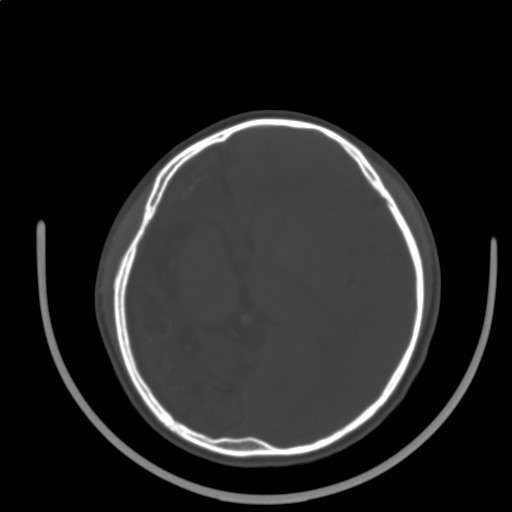

标题: PED3416:F,12Y,智力下降,学习成绩差,8个月时发过高烧。

右侧半球萎缩,软化,多量脑回样钙化,考虑颅面血管瘤病,建议dsa检查

右侧半球萎缩,软化,多量脑回样钙化,同侧颅盖板障增宽,考虑颅面血管瘤病,建议dsa检查与化脓性脑膜炎后遗改变鉴别。